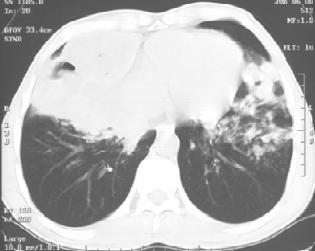

2.胸部X线检查 变化较大,不具有特异性,通常于吸入1~2小时后即能见到两肺散在边缘模糊的不规则片状阴影。肺内病变分布与吸收时体位有关,常见于中下肺野,以右肺多见。发生肺水肿,则两肺出现的片状、云絮状阴影融合成大片状,从两肺门向外扩散,以两肺中内带为明显;这与心源性急性肺水肿的X线表现相似,但心脏大小和外形正常,无肺静脉高压征象(图1-4)。

图1-4 男性,诊断为吸入性肺炎